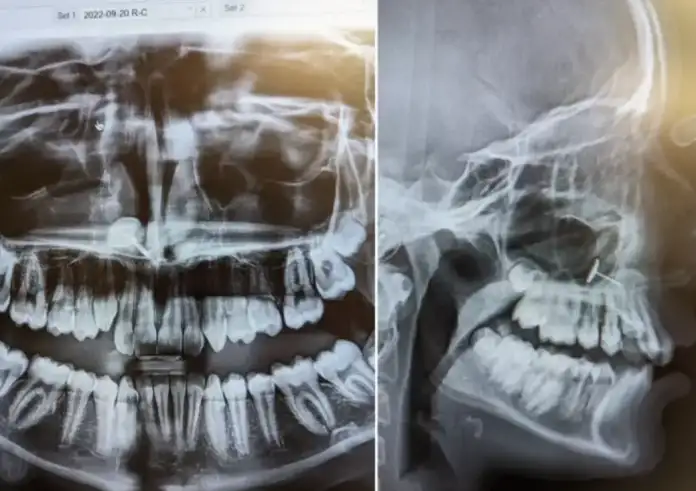

Πήγε την κόρη της για σιδεράκια – Η ακτινογραφία αποκάλυψε ένα μυστικό που έκρυβε για μήνες

Μια ρουτίνας επίσκεψη σε ορθοδοντικό μετατράπηκε σε απρόσμενη… ανακάλυψη για μια μητέρα στην Πολιτεία της Ουάσινγκτον, όταν η ακτινογραφία της...